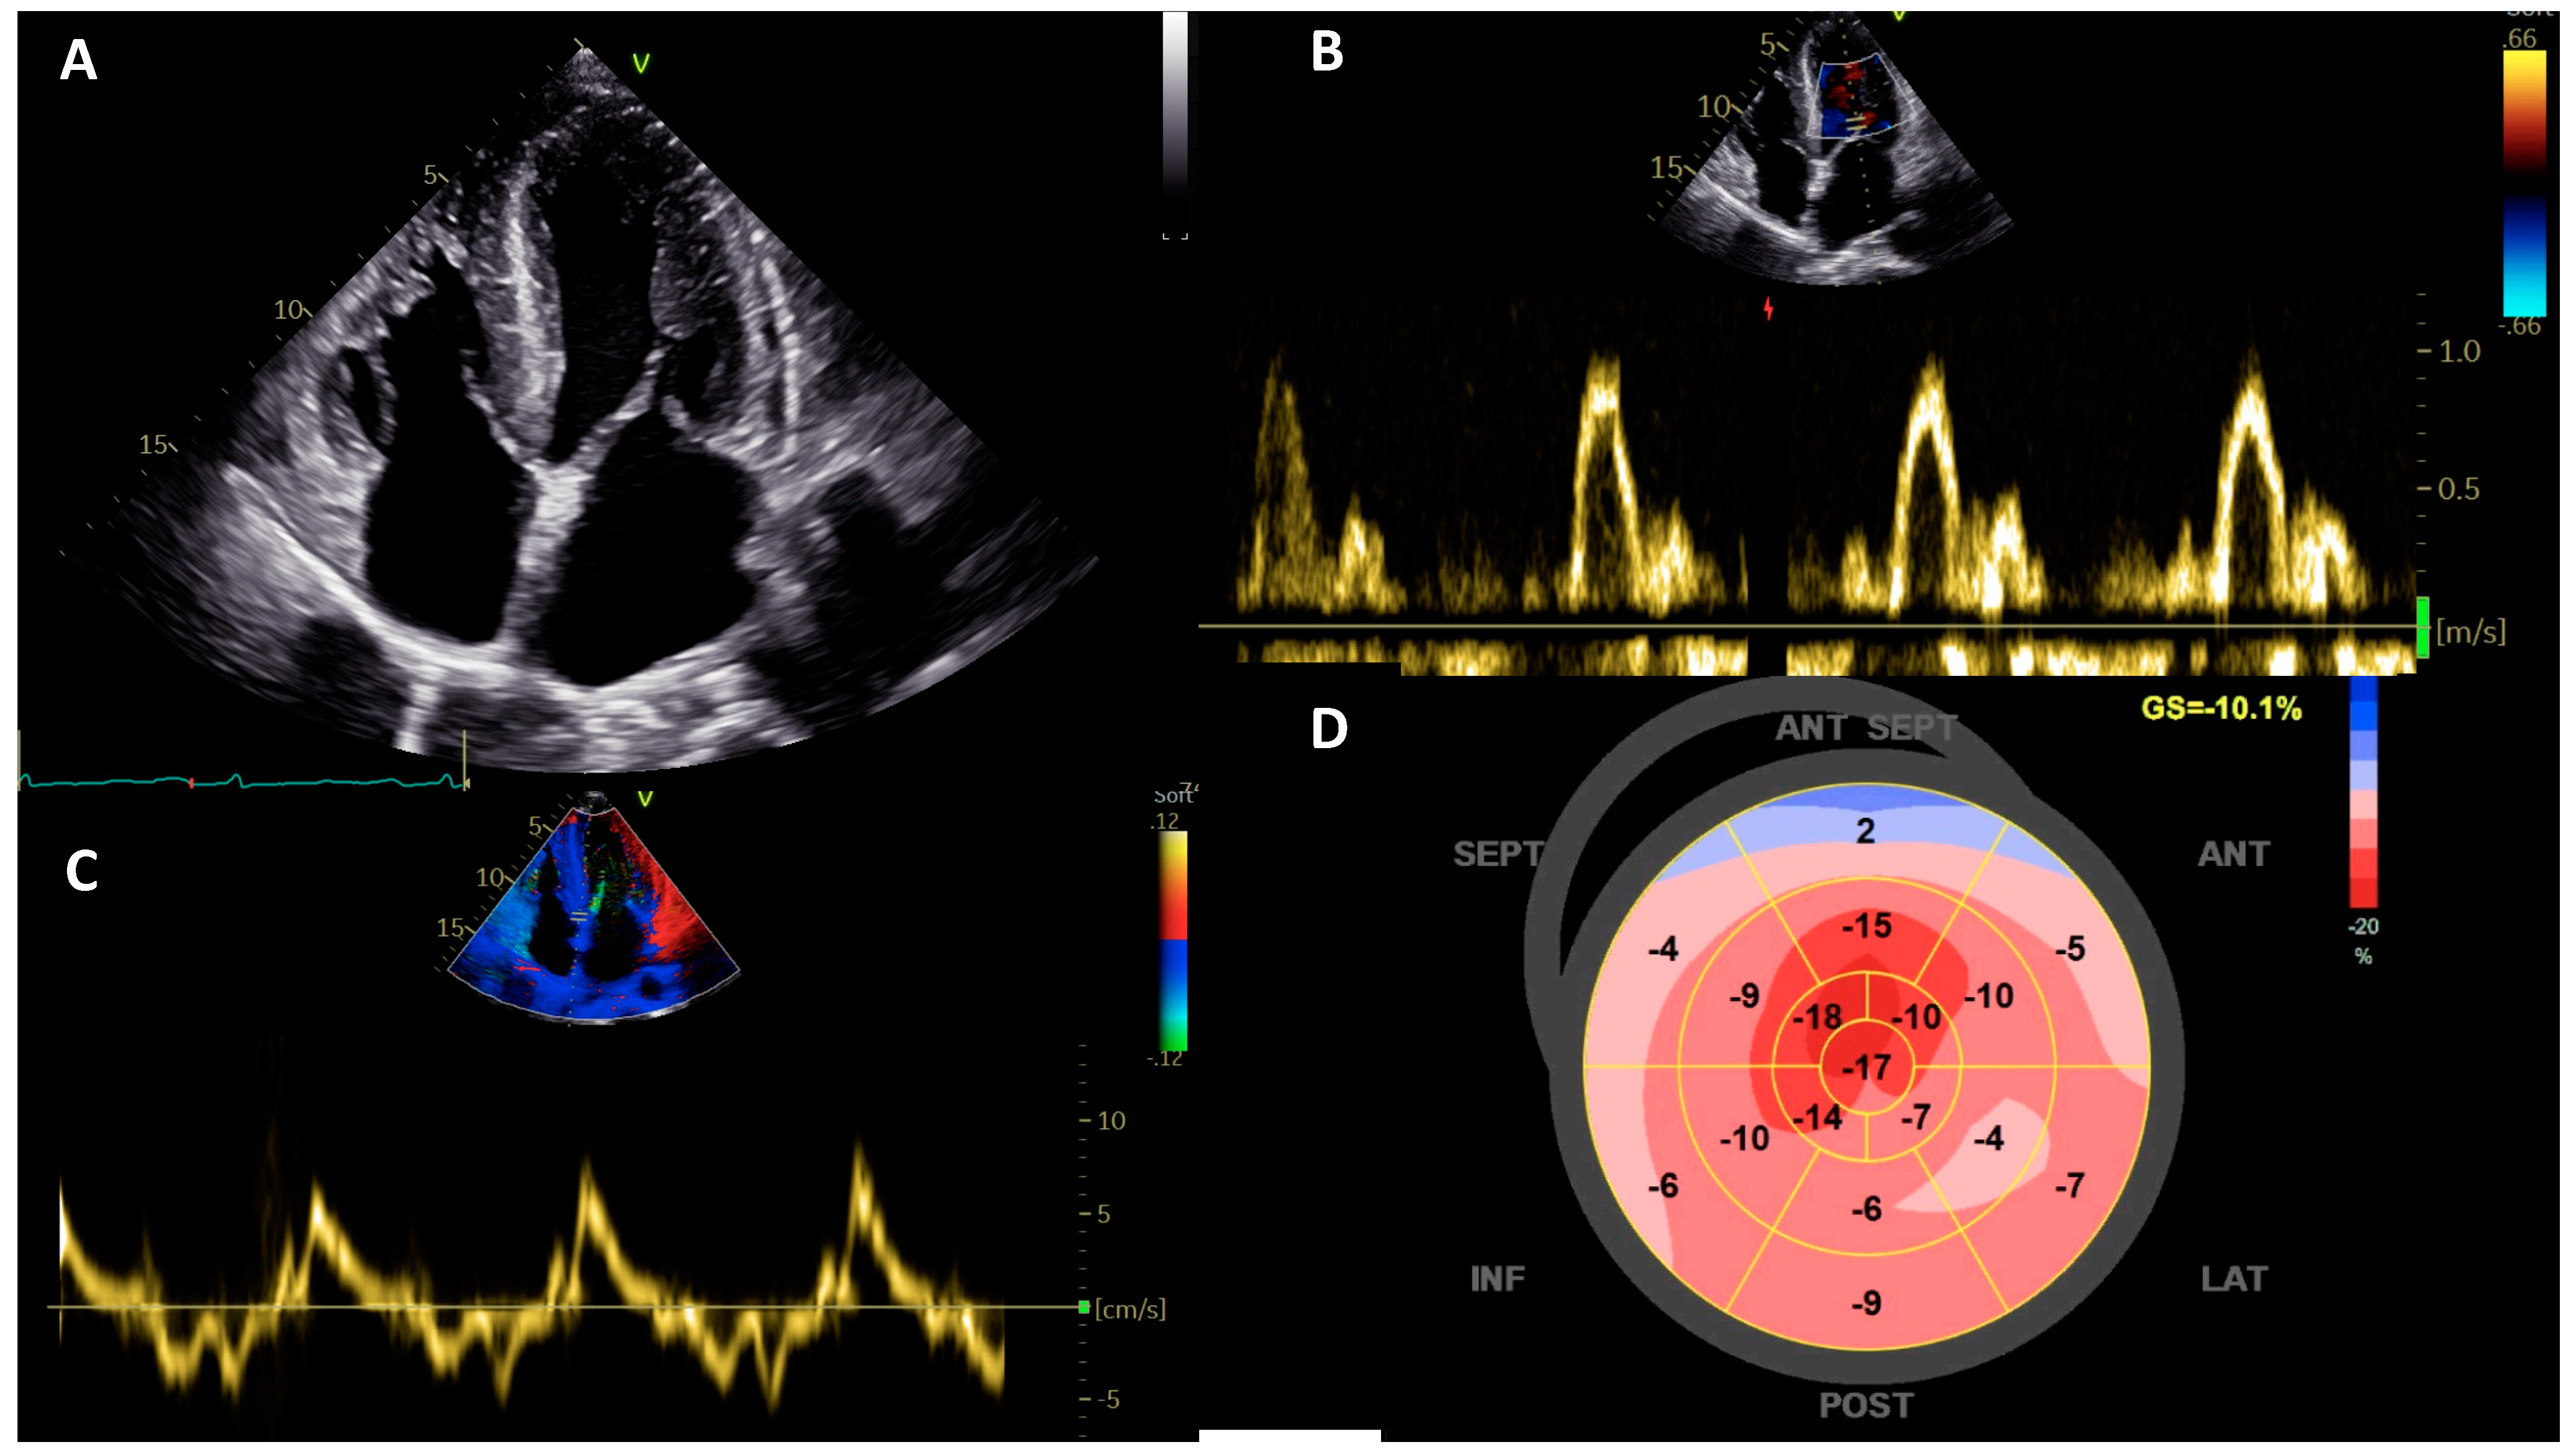

| Fabry disease | 2D: Predominant severe concentric LVH with preserved LVEF and progressive increase in LV volumes. Strain imaging: Reduced longitudinal strain in the basal posterior-lateral wall; impaired LV subendocardial longitudinal strain at multilayer strain analysis. | ECG: short PR, conduction abnormalities. Extracardiac involvement: cutaneous (angiokeratoma, hypohidrosis), neurological (acroparaesthesiae, stroke-like events), renal (proteinuria, ned-stage kidney failure), ocular (corneal dystrophy), gastrointestinal (abdominal pain, vomiting, diarrhoea). |